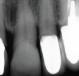

Case 1: 46 years old Male patient, ASA 1, presented for the evaluation and the treatment of tooth #36. On clinical examination the tooth was sensitive to percussion and palpation. The radiographic examination showed a very large radiolucency on both mesial and distal roots, a separated instrument in the mesio-lingual canal. The diagnosis of previously initiated with symptomatic apical periodontitis was made, and the endodontic treatment was indicated.

Following aesthesia and rubber dam placement, access was performed, and canals were located. The coreonal fragment was removed and the apical fragment was bypassed. The canals were instrumented using Edge endo X7 files (EdgeEndo) to size 35.04 in the mesial canals and 40.04 in the distal canal.

Canals were obturated using hydraulic condensation using EdgeBioCeramic Sealer (EdgeEndo). Bioceramic cement was used for its antibacterial and bioactive properties. The one year follow up shows a complete healing of the lesion.